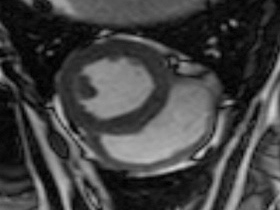

Easy-Trigger ist ein Medizinprodukt für die Herz- und Gefäßbildgebung in der Magnetresonanztomographie (MRT), das bifunktional bei Ungeborenen und Erwachsenen eingesetzt werden kann. Als weltweit erstes und einziges MRT-taugliches Doppler-Ultraschallgerät ermöglicht es erstmals Kombinationsuntersuchungen von MRT und Ultraschall. Der Ultraschallkopf wird auf dem Bauch oder über dem Herzen des Patienten platziert. Es ermöglicht erstmals die zeitliche Abstimmung der Herzaktion von ungeborenen Kindern mit dem MRT und damit MRT-Untersuchungen des kindlichen Herzens. Des Weiteren kann es zur Überwachung der Ungeborenen bei MRT-Untersuchungen von Schwangeren eingesetzt werden. Durch die Verwendung der Doppler-Ultraschall-Technik ist die Anwendung am Erwachsenen im Vergleich zum EKG robuster, einfacher und sogar bei höheren Feldstärken einsetzbar, bei denen das EKG nicht mehr zuverlässig arbeitet.

- Kording F, Yamamura J, Much C, Adam G, Schoennagel B, Wedegärtner U, Ueberle F.:

Evaluation of an MR Compatible Doppler-Ultrasound Device as a New Trigger Method in Cardiac MRI: A Quantitative Comparison to ECG.

Biomed Tech (Berl). 2013 Sep 7.